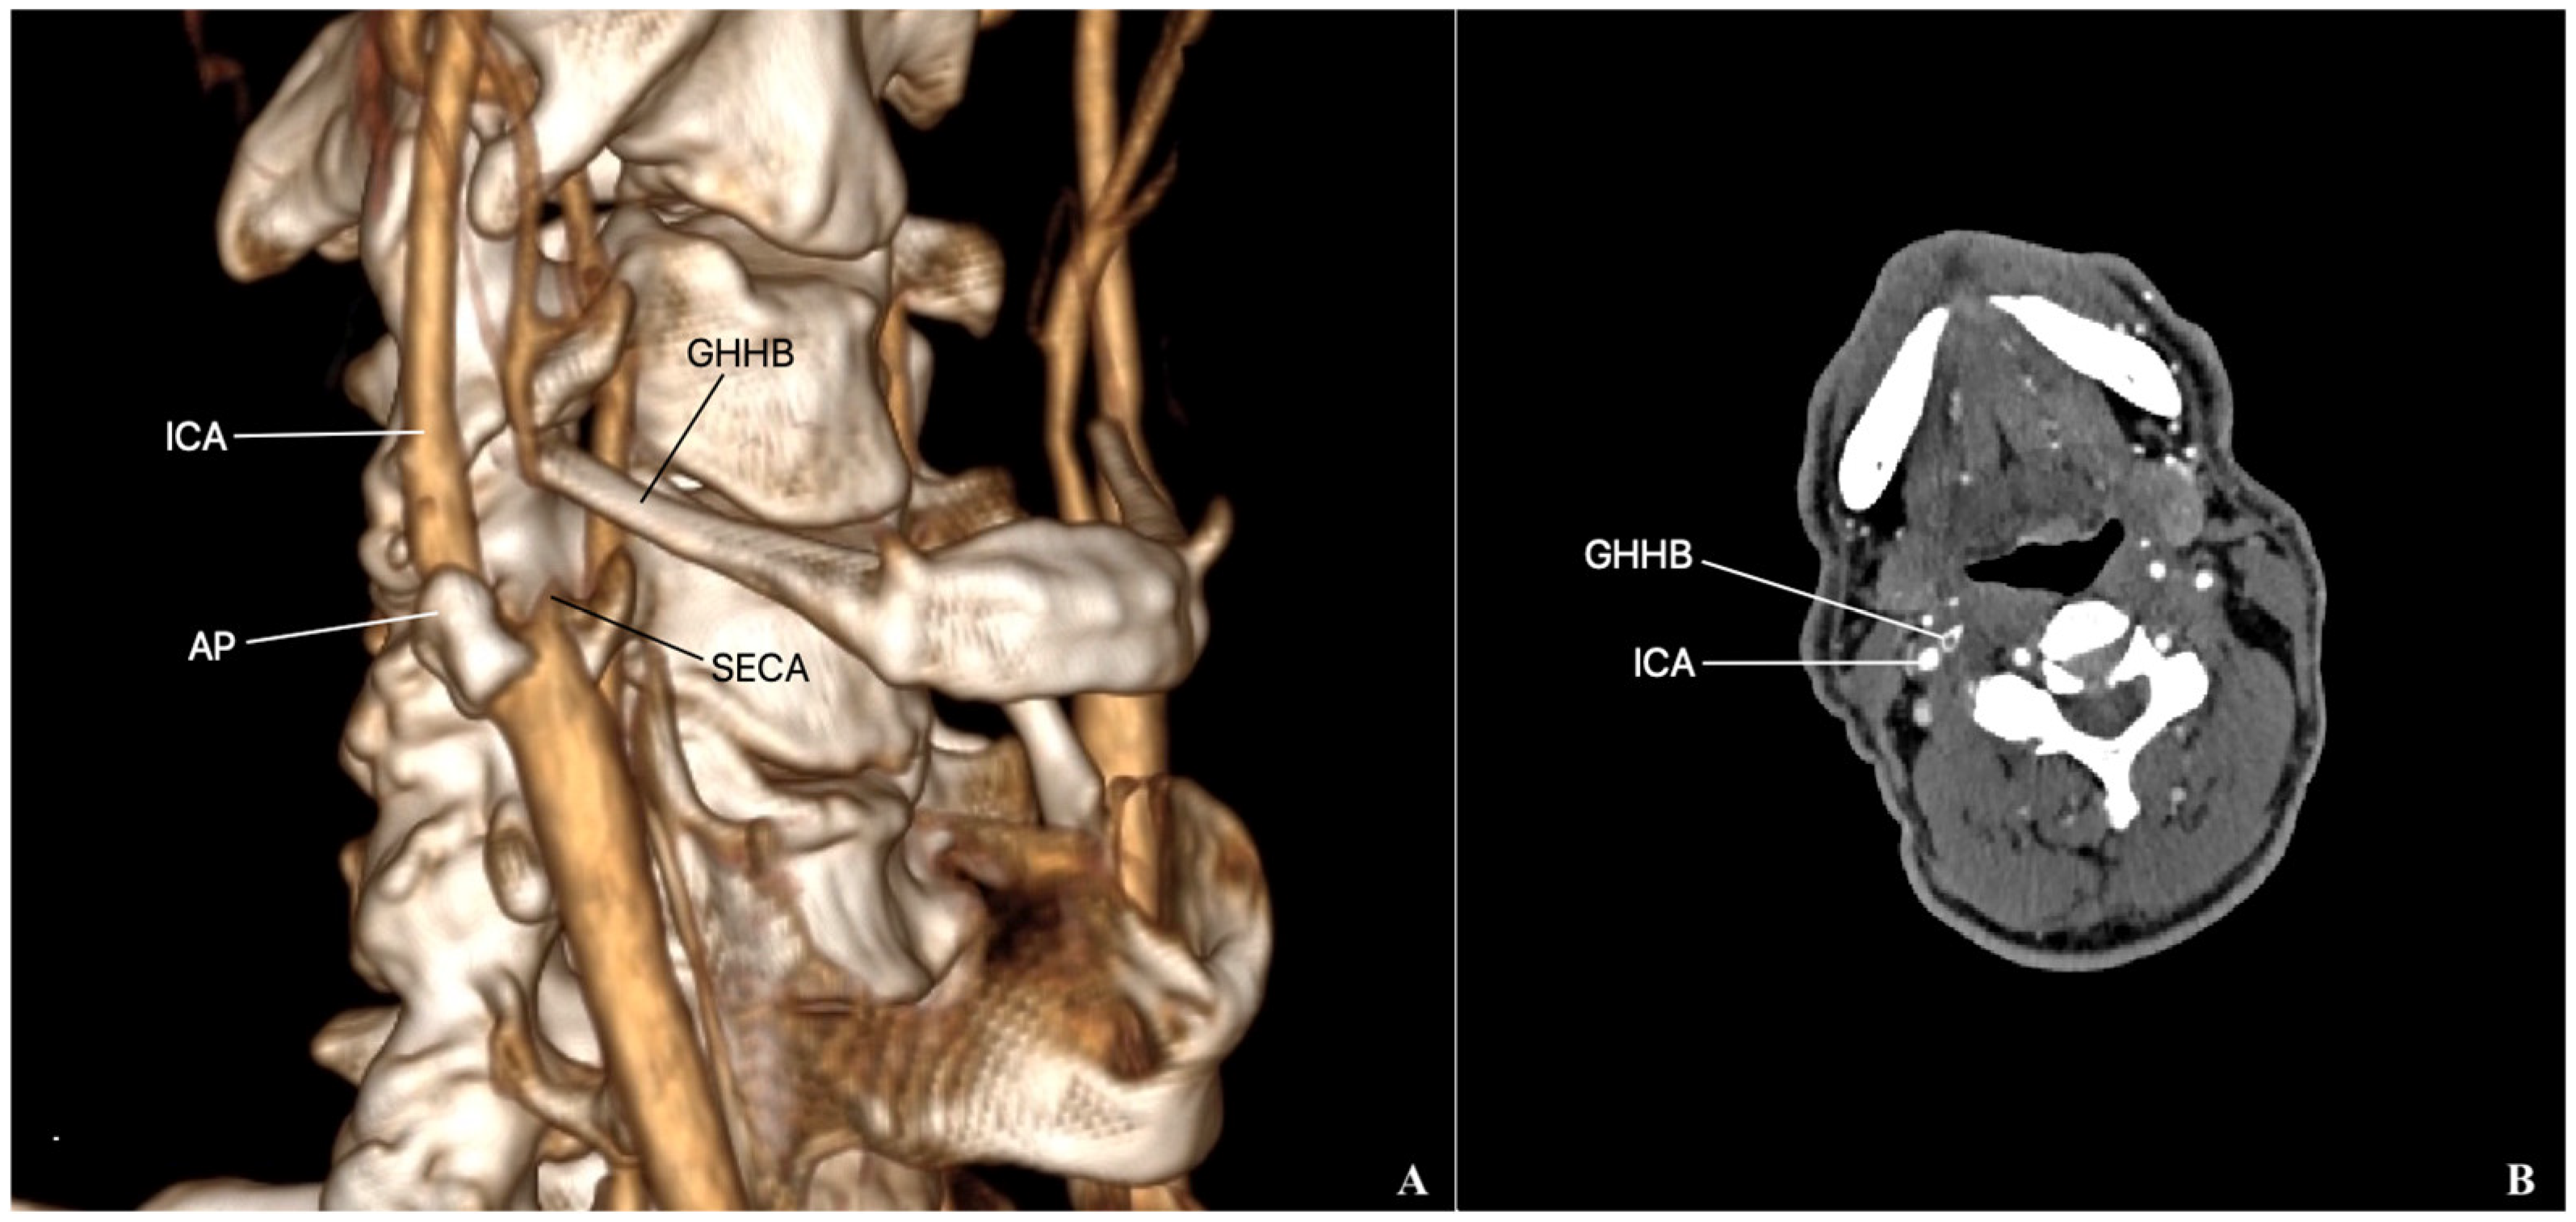

External Carotid Artery Entrapment by the Hyoid Bone Associated with an Atherosclerotic Stenosis of the Internal Carotid Artery

2. Case Presentation

- Keshelava, G.; Robakidze, Z. Iternal carotid artery stenosis and entrapment by the hyoid bone. Eur. J. Vasc. Endovasc. Surg. 2024, 68, 422. [Google Scholar] [CrossRef]